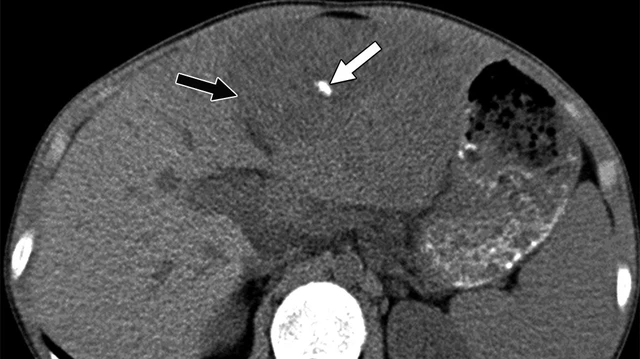

Vôi hóa gan có thể ảnh hưởng đến chức năng gan và gây ra các biến chứng nguy hiểm như viêm gan mạn tính, xơ gan, và thậm chí ung thư gan. Kích thước nốt vôi hoá gan giúp bác sĩ kết luận về nguy cơ ảnh hưởng đến chức năng gan.

Vôi hoá gan là một bệnh lý thường gặp ở những bệnh nhân có tiền sử mắc bệnh viêm gan. Nốt vôi hóa trong gan ít hay nhiều và mức độ tổn thương đối với gan cũng như sức khỏe của người bệnh là khác nhau trong từng trường hợp.